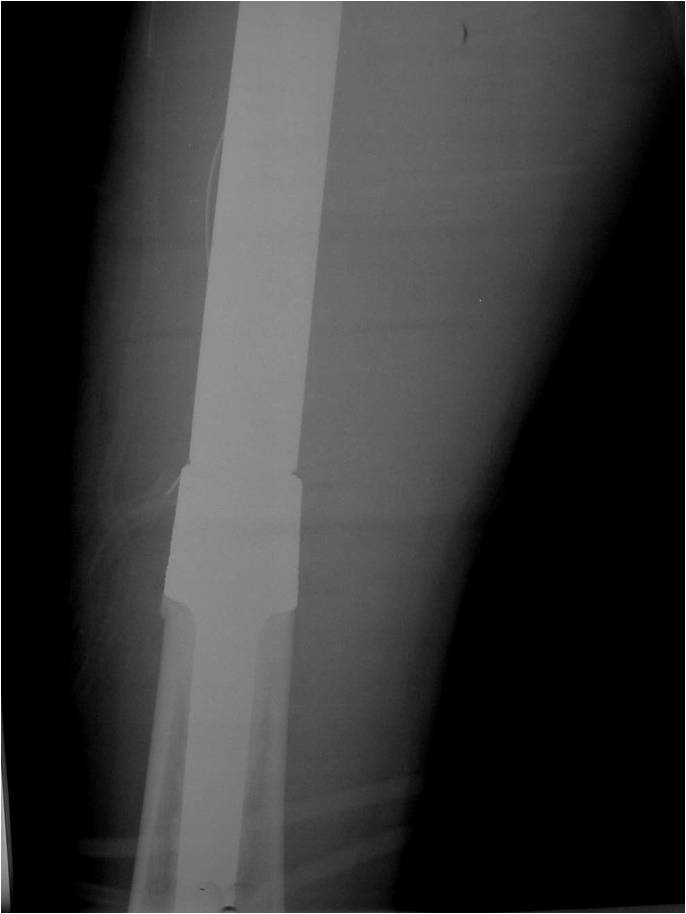

Radiographic Presentation

- Permeative or moth eaten bone destruction

- Ill defined and malignant appearing

- Bony changes are often subtle

- Soft Tissue Mass in 90% of of cases

- Periosteal Reaction in 50% of cases

- Due to irritation, edema, tumor permeation

- Onion Skin (colic pattern of irritation)

- Hair on End (rapid continuous lifting of periosteum)

- Reactive Bone Sclerosis is rare but occurs in 10% of cases

- No cartilage or bone production by tumor

- Pathologic fracture in 10-15%